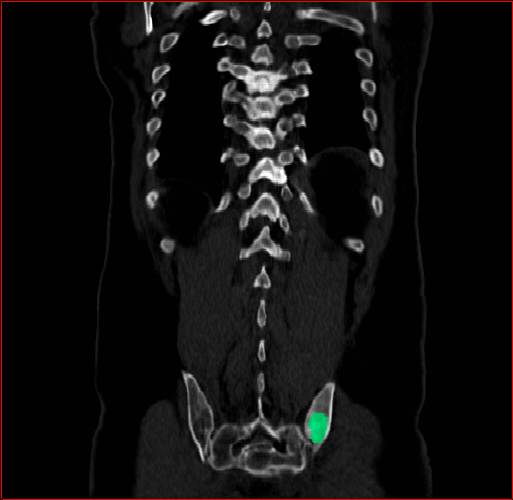

Figure 3 shows the generalizability of MAISI-v2 ControlNet for different body regions and voxel sizes. Figure 4 shows qualitative results for MAISI-v2 ControlNet on 5 types of tumors.

Lung Tumor

0.75×0.75×0.60.75\times 0.75\times 0.6

mm

512×512×512512\times 512\times 512

Panc. Tumor

1×1×11\times 1\times 1

Figure 4: MAISI-v2 segmentation-guided results for five types of tumors. We show results for different voxel spacing and volume size to demonstrate the flexibility of MAISI-v2. Different Hounsfield Unit window is used to better show the contrast between tumor and normal tissues.